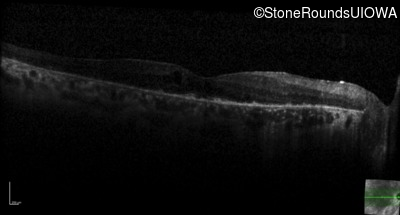

Optical Coherence Tomography - Right - 20/40

Exemplar / OCT Stack